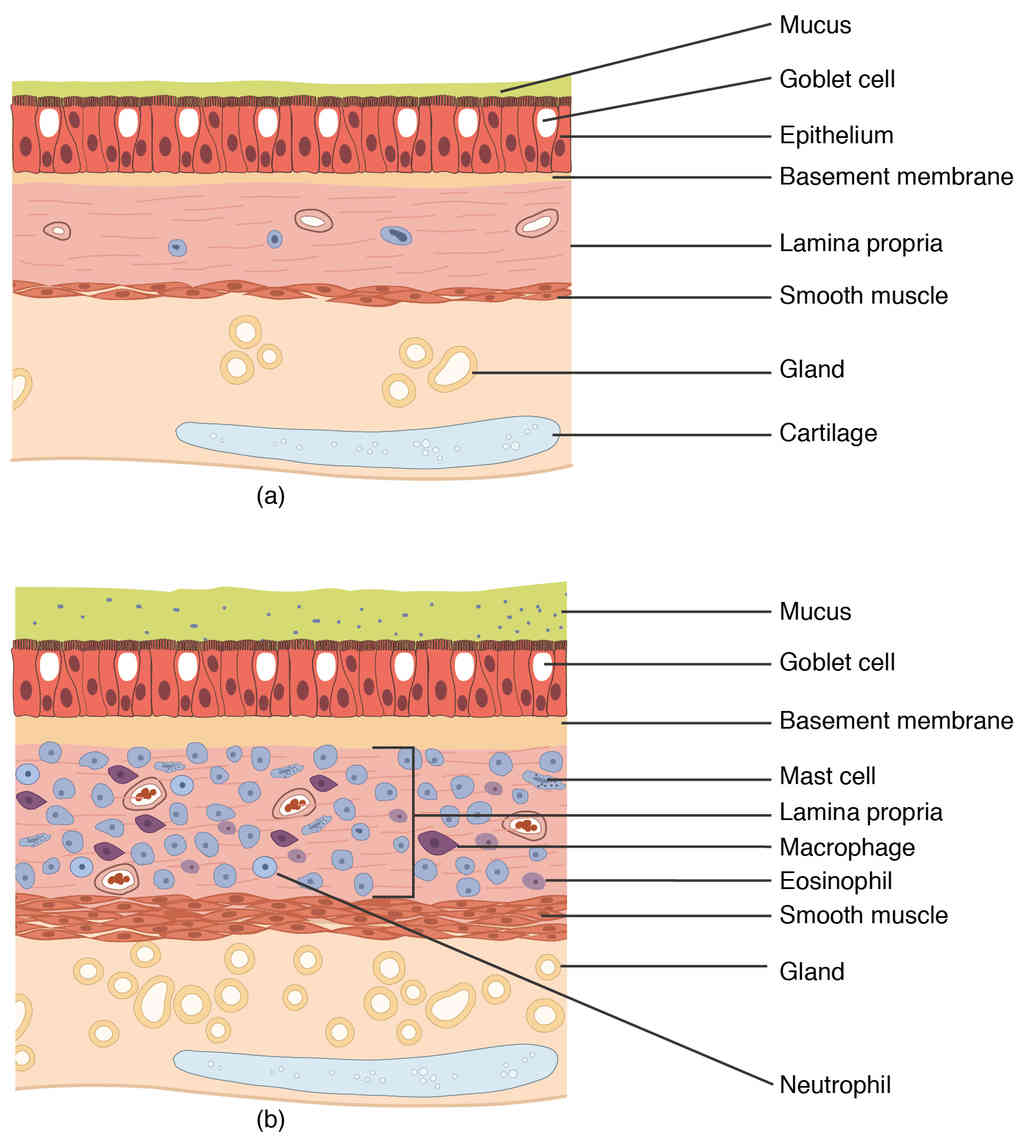

Anatomy, Physiology and Histology

This page is under construction. For now, it is just a resource of the images found in the OpenStax Anatomy and Physiology Handbook. It wil slowly change into a revision tool. Each slide has a number. Use this to refer to the slide. When completed, it will have an unlabelled section, with labelled slides in parallel. On the unlabelled slides, write your answer and use the labelled slide to assess yourself. Keep track by also noting the number on each slide. Improvement at each attempt is important, more so than full marks on a first attempt.